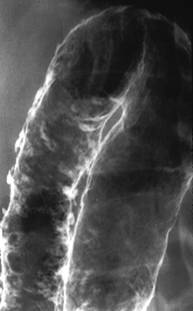

Examenul baritat cu dublu contrast evidentiaza ulceratiile aftoide sub forma unor mici depozite de substanta de contrast inconjurate de un halo transparent. Mai pot fi evidentiate leziuni unice sau multiple despartite de zone sanatoase- aspectul de "pietre de pavaj", stenoze pana la "semnul sforii", fistule. Cand exista suspiciunea de stenoza, examenul baritat este contraindicat.

Boala Crohn- ulceratii extensive Semnul

sforii in boala Crohn

ale peretelui colonului, inflamatia mucoasei ileala